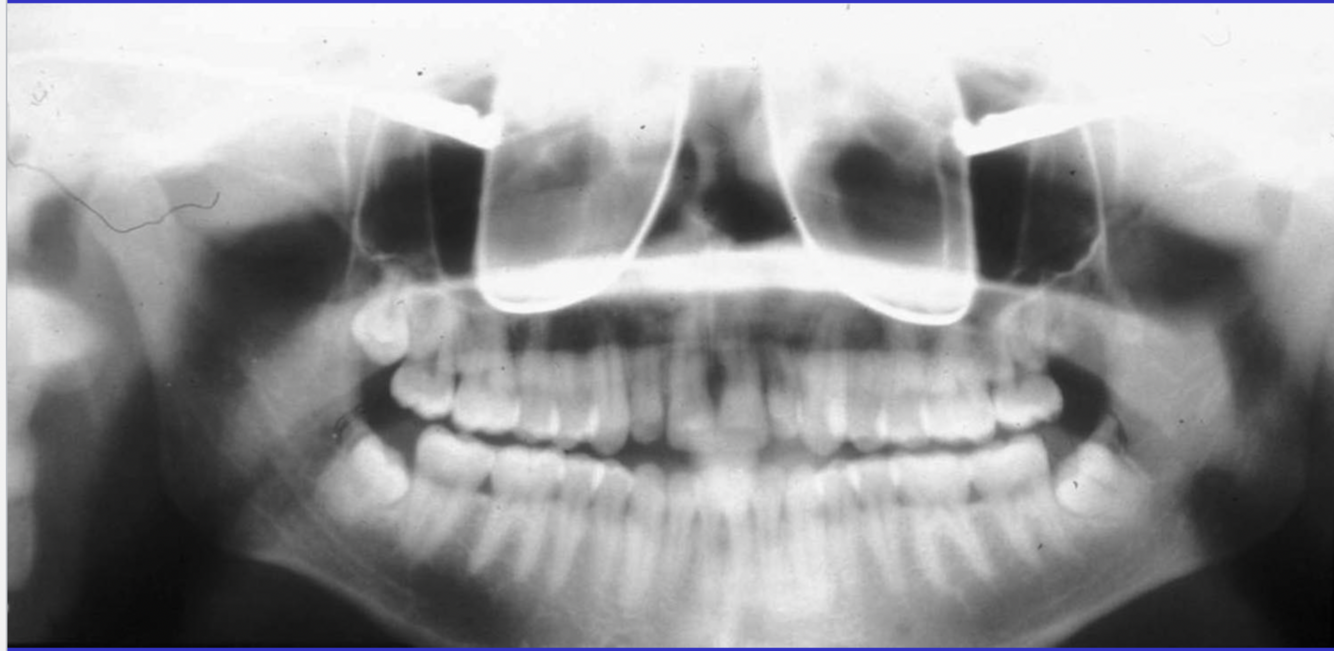

What are some errors that can be seen in this radiograph? What is the cause?

1. flat occlusal plane or reverse curvature 2. roots of maxillary anterior teeth are blurred 3. rami/condyles tipped laterally 4. condyles close to or cut off the side of image 5. hard palate superimposed on maxillary apices cause: chin up